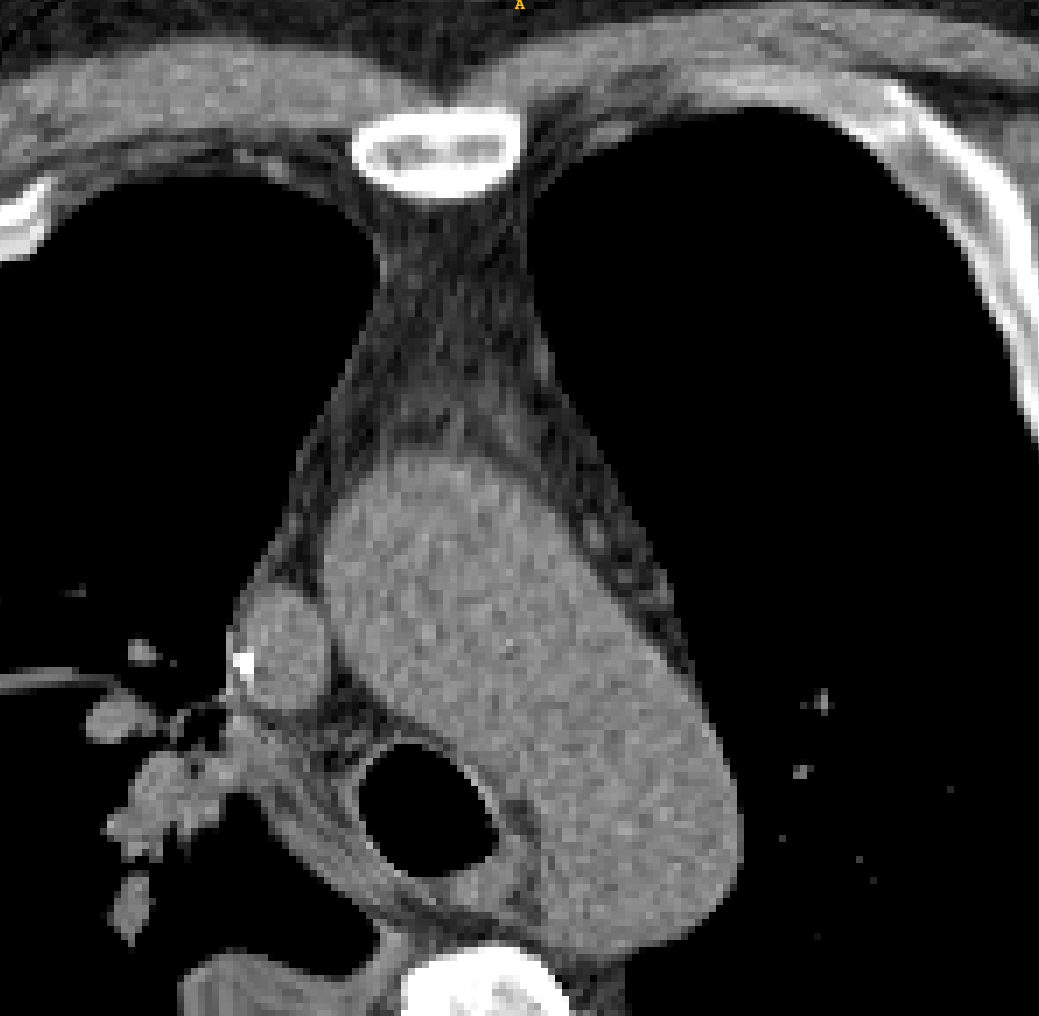

Refer to caption

Figure 1: Difference between large deformation chest images (up) and small deformation brain images (down)

In recent years, many methods use deep learning to handle non-rigid registration tasks. Some supervised deep learning methods are proposed. Those methods require ground truth of the registration field, which is expensive and hard to obtain. STN[19] proposes a method that achieves the nonrigid registration process by sampling from the moving image. Since then many researchers focus on the unsupervised deep learning algorithms, and VoxelMorph[11, 10, 7, 6] is one of the most commonly used methods. The VoxelMorph formulates registration as a function that maps an input image pair to a deformation field. However most unsupervised registration algorithms are designed for brain image registration, which has a smaller deformation, cleaner background, and less region overlap compared with chest CT registration (Figure 1). They cannot achieve satisfactory registration results in the presents of large displacement between input images.